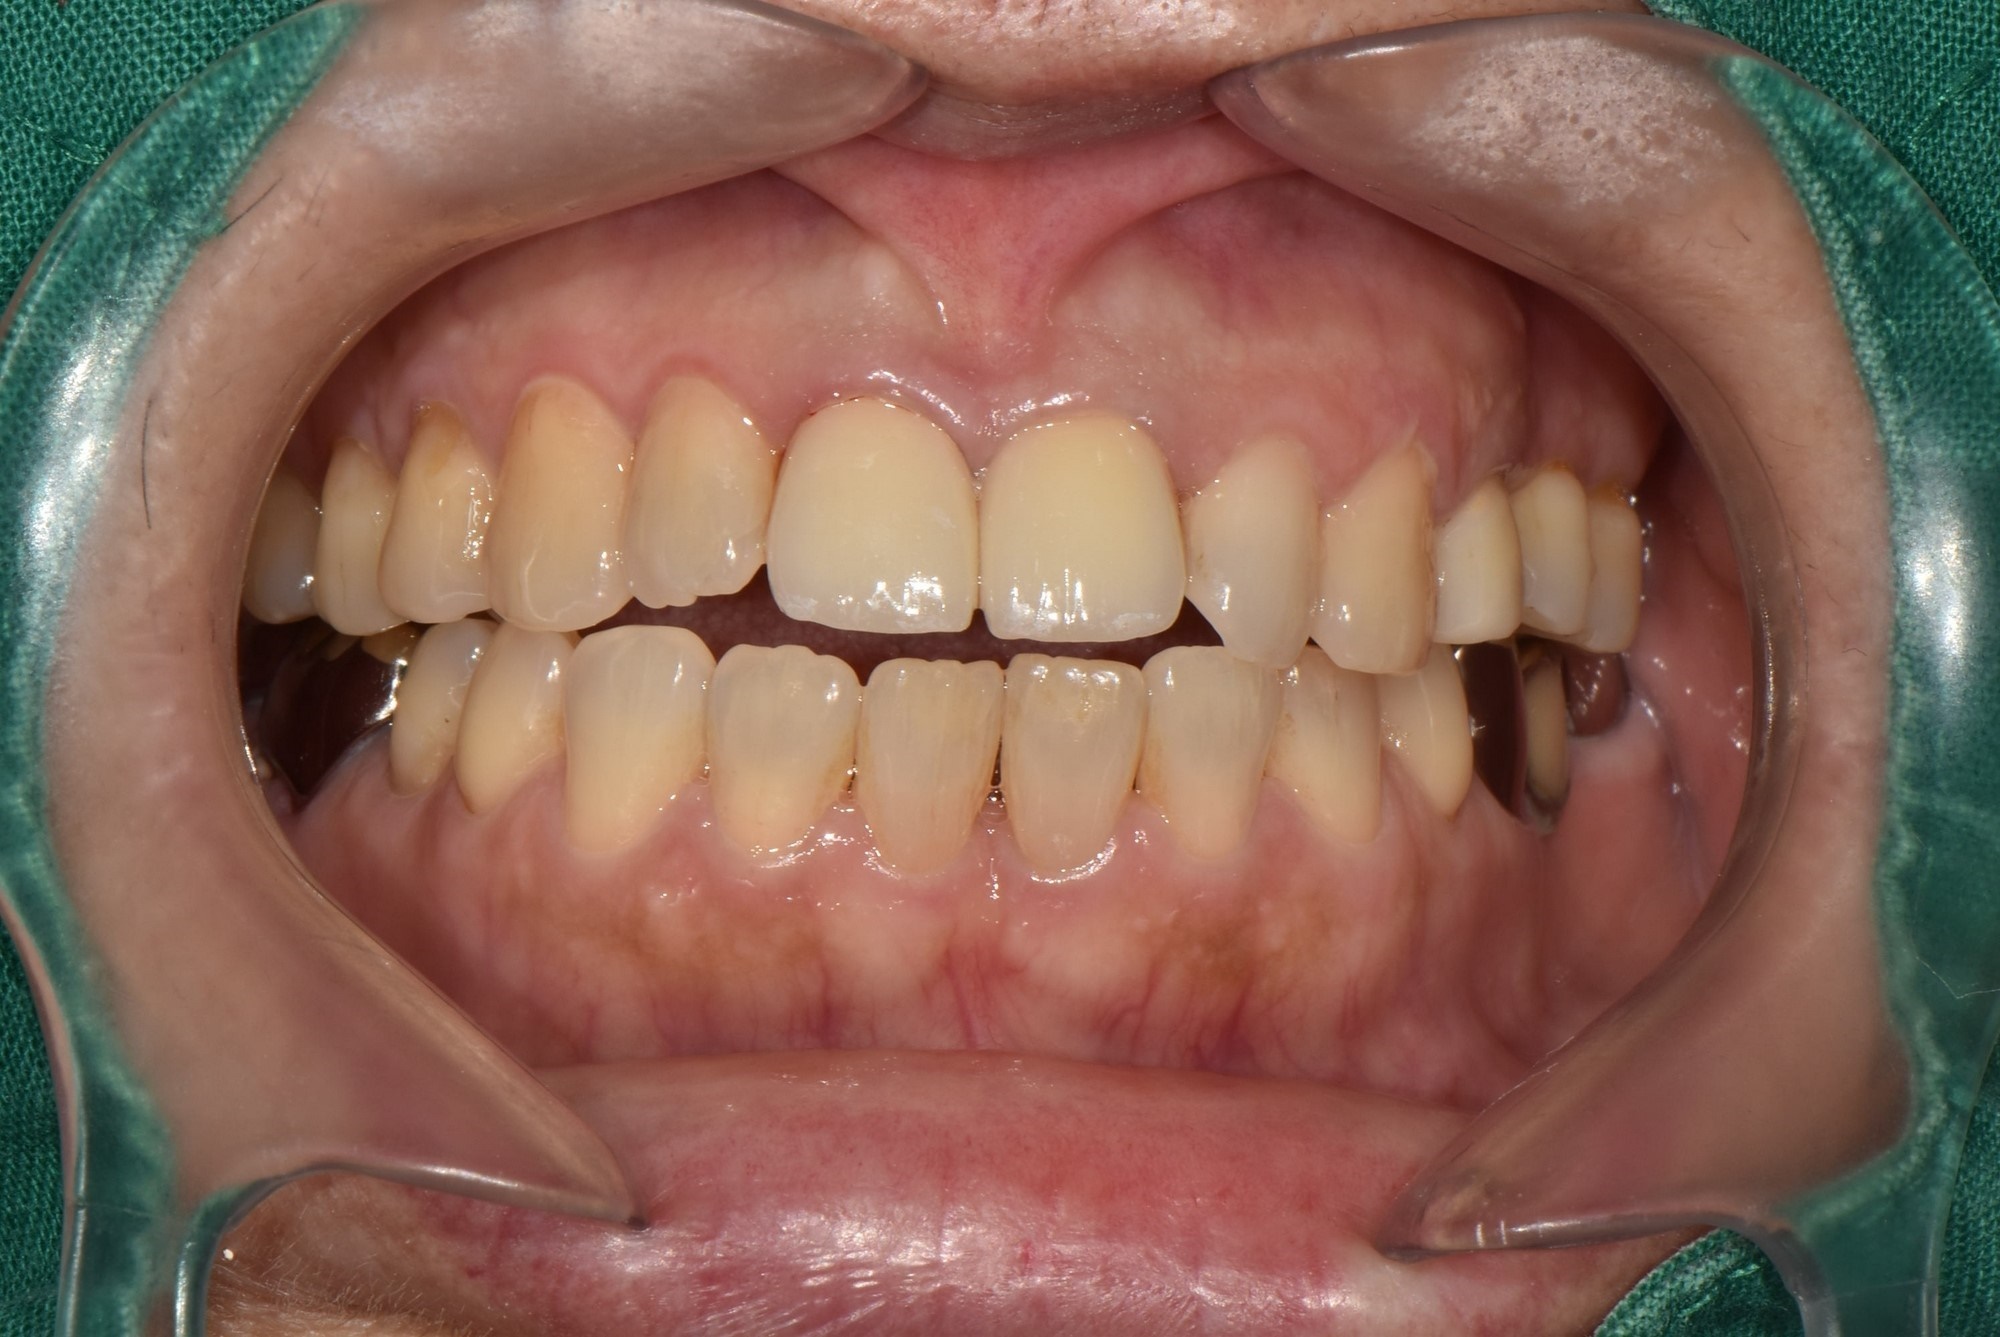

수술 전

수술 후

상하악 구치부 임플란트 식립사례

전후사진

전치부 크라운 수복 사례